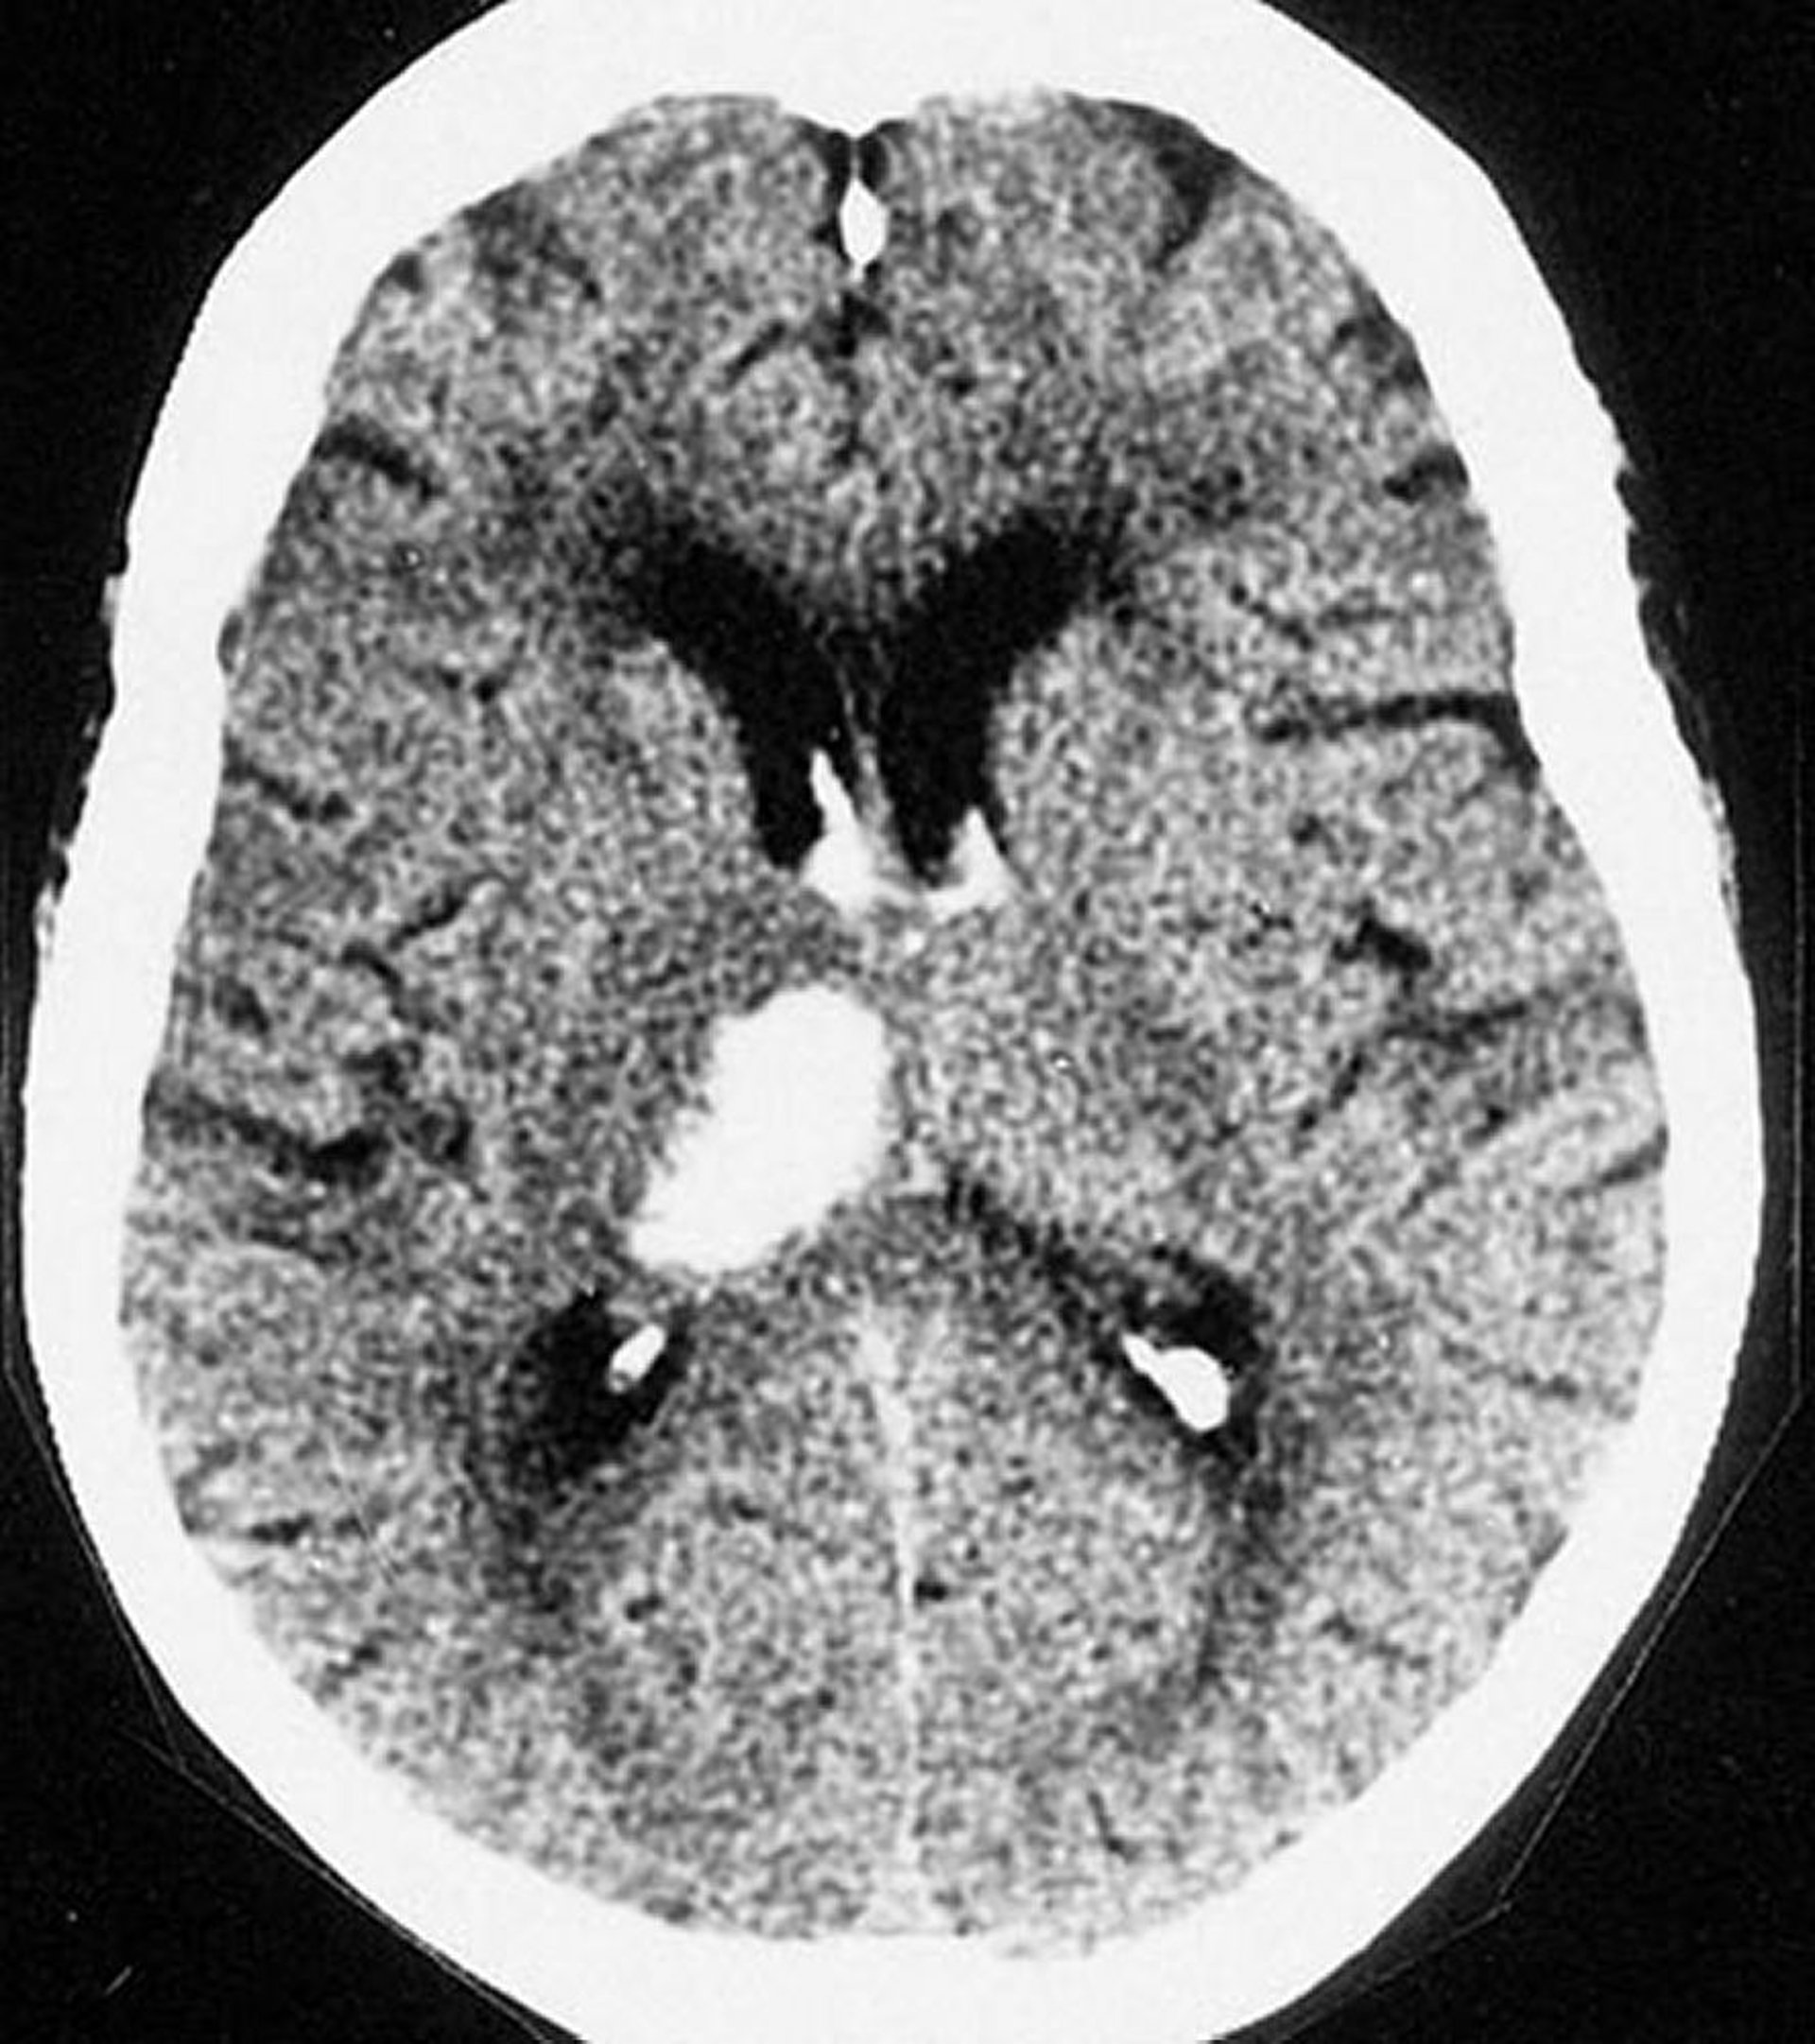

Thalamic Intracerebral Hemorrhage

This CT scan shows a hemorrhage in the thalamus. Intracerebral hemorrhages commonly occur in the thalamus and within the basal ganglia.

By permission of the publisher. From Furie K, et al. In Atlas of Clinical Neurology. Edited by RN Rosenberg. Philadelphia, Current Medicine, 2002.